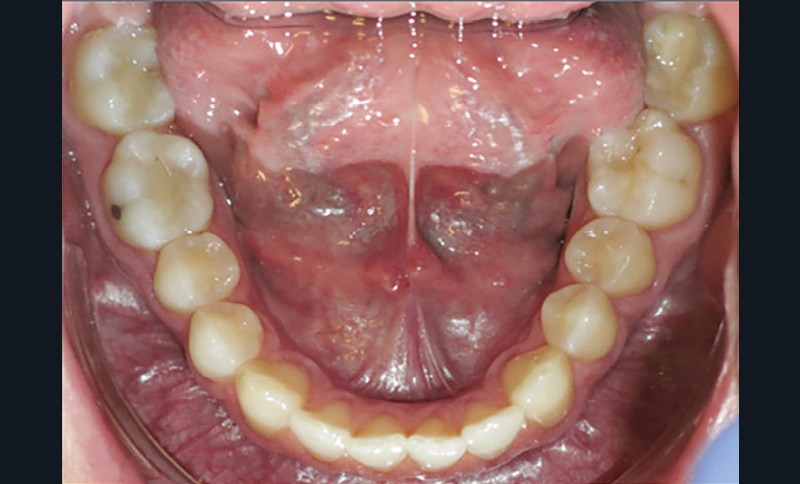

Examen endobuccal (fig. 2a-e)

L’arcade maxillaire est asymétrique, en hémi-lyre droite. Elle présente une mésio-position du secteur 1 en lien avec un encombrement antérieur estimé à 4 mm, se traduisant par une palato-position de la 12 et une rotation de la 11. On observe également des mésio-rotations des premières molaires et une palato-version incisive. L’arcade mandibulaire est ellipsoïde et présente un léger encombrement incisif (1 mm).

Concernant les relations occlusales, on observe une classe II complète subdivision droite. Le surplomb est absent et le recouvrement augmenté, estimé à 4 mm, a provoqué une usure des bords libres de 11 et 21 par attrition. Dans la dimension transversale, on constate une endoalvéolie maxillaire, ainsi qu’une concordance des médianes incisives entre elles, mais toutes deux déviées à droite par rapport au plan sagittal médian.